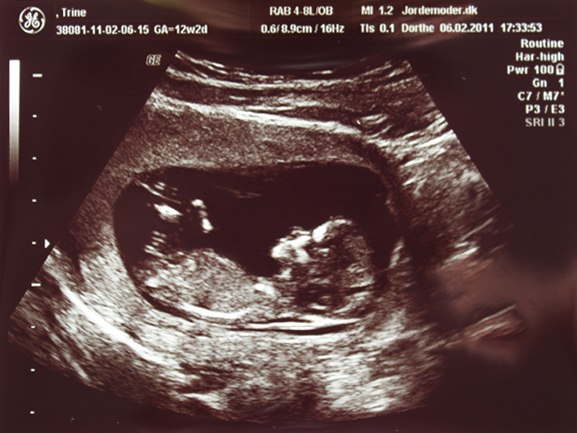

Jeg er i dag 12+2 og kæresten og jeg havde købt os til en scanning da han ikke kan komme med når jeg skal til NF på Tirsdag.. hehe..

Da vi kom derind kom der hurtigt billede på og lige der kunne vi se den meste fantastiske lille skabning.

Det var helt vildt at se den lille en som der ligger derinde og hygger sig. Den havde vist også lidt hikke, der kom der hvert fald nogle hop en gang imellem, vi fik også et lille vink, og to 2 havde den også vendt ryggen til os..

Hende som scannede os sagde at alting så såååå fint ud.. den målte 5,7 cm fra hovede til hale, og størrelse på hovedet og lår ben var også super flot

Iiih hvor var det virkelig vildt at se den lille trut der ligger der inde..